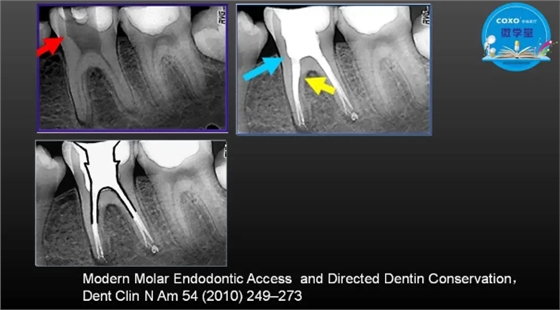

主任医师,牙体牙髓副主任, 广东省口腔医院牙体牙髓科 主任医师。2003年硕士研究生毕业,研究方向为牙体牙髓病学,擅长于牙体牙髓病的诊断、龋齿、牙髓炎、根尖周病的治疗以及前牙美容修复。